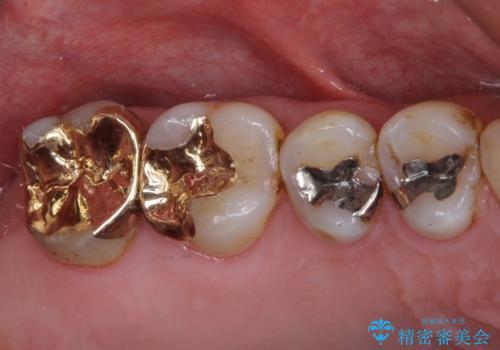

銀歯や虫歯を治したい ゴールドインレーによるむし歯治療